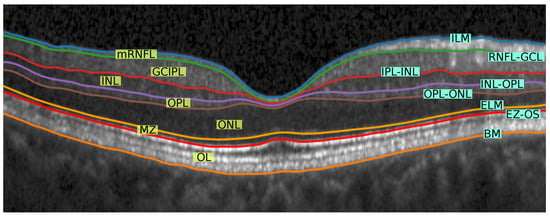

Our segmentation method consists of two cascaded U-Net-like architectures, as shown in Figure 1. The first network, termed RS-Net (retinal segmentation network), is responsible for segmentation of the retina from a full OCT B-scan. In its simplest form, this is the retinal tissue between the inner limiting membrane (ILM) and Bruch’s membrane (BM) as boundaries. The trained network takes a preprocessed OCT B-scan as input and produces a three-class output: purple region (above ILM), green region (retinal region) and yellow region (below BM) (Figure 1). The output of RS-Net and the original input serve as the input for the second network. The second network, the intraretinal layer segmentation network (IS-Net), takes the two-channel input and generates a 9-class output providing boundaries for 8 different intraretinal layers and membranes: ILM—inner limiting membrane, mRNFL—macular retinal nerve fiber layer, GCL—ganglion cell layer, IPL—inner plexiform layer, GCIPL—macular ganglion cell/inner plexiform layer, INL—inner nuclear layer, OPL—outer plexiform layer, ONL—outer nuclear layer, ELM—external limiting membrane, MZ—myoid zone, EZ—ellipsoid zone, OS—outer segment, RPE—retinal pigment epithelium, OL—outer layer and BM—Bruch’s membrane (Figure 2).

In this section, we compute the standard OCT parameters based on the segmented layers using the proposed method. Here, we are focusing on five standard thickness parameters within a 5 mm circular region from the foveal center. The parameters are described in Figure 2, and additionally we provide data for the ganglion cell complex (GCC, tissue between ILM and IPL-INL boundary) and total macular thickness (TM, between ILM and BM).

Figure 2. Visual representation of different retinal layers and boundaries after segmentation. Our method segments 9 different regions (7 highlighted with yellow background on the left side of the image and other two region are: above ILM and below BM) from 8 different retinal boundaries (highlighted with cyan background on the right side of the image). Layer abbreviations are positioned within their respective layer; boundary abbreviations are positioned on top of their respective segmentation lines. Abbreviations: ILM—inner limiting membrane, mRNFL—macular retinal nerve fibre layer, GCL—ganglion cell layer, IPL—inner plexiform layer, GCIPL—macular ganglion cell/inner plexiform layer, INL—inner nuclear layer, OPL—outer plexiform layer, ONL—outer nuclear layer, ELM—external limiting membrane, MZ—myoid zone, EZ—ellipsoid zone, OS—outer segment, RPE—retinal pigment epithelium, OL—outer layer and BM—Bruch’s membrane.